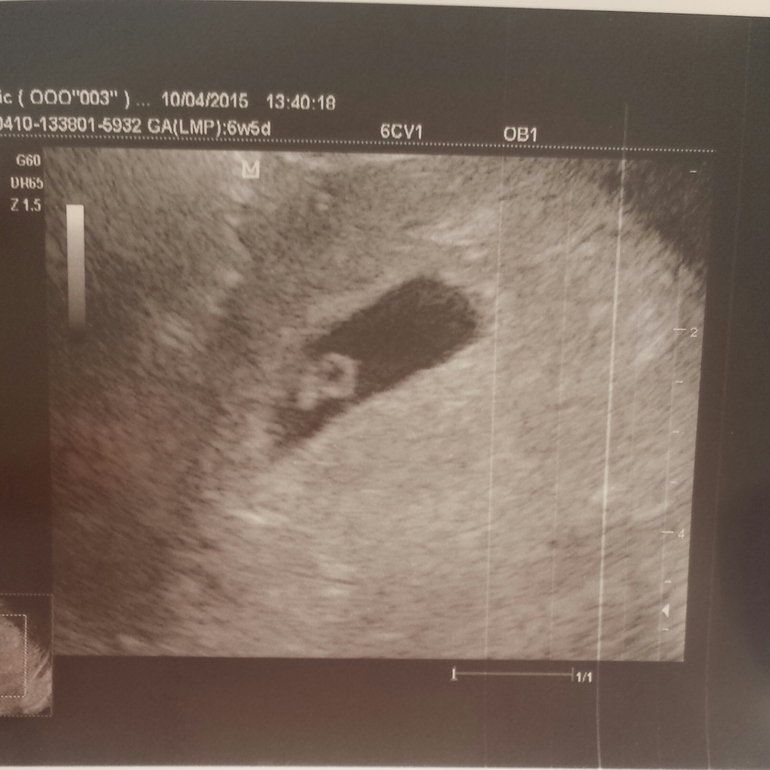

dee71d3627d413032a398de5a73adc3d.jpg 9aedcc1f06b9d387c3249e403123ad50.jpg Первое фото в 6н5д, там слева эмбрион, а справа как кружочек желточный мешок, второе фото вчера

22.04.2015

На втором фото уже и малышастик виден)))